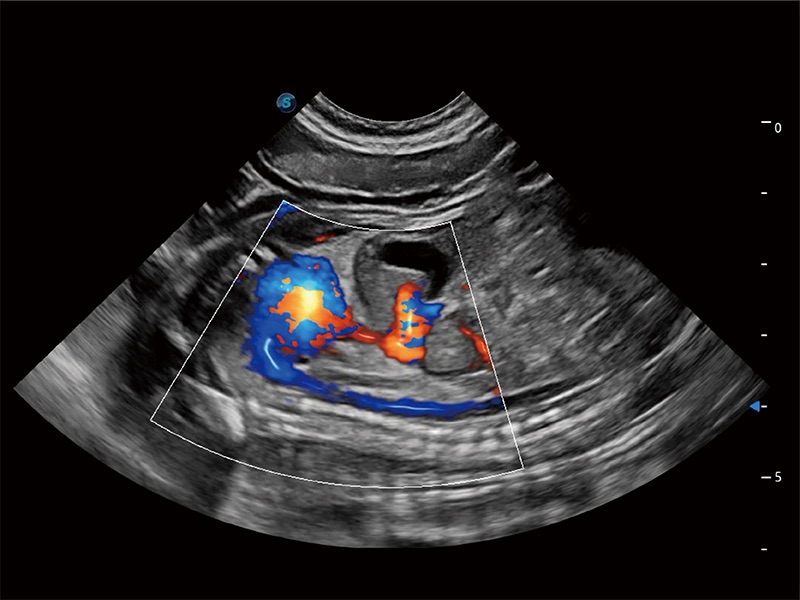

(犬)二腔心血流

• Bright Flow 立体血流成像

在传统二维血流成像的基础上,呈现血流的立体感,具有动感的生命力之美。即便是微小的血管也能轻松应对,提高了血流的视觉敏感性。